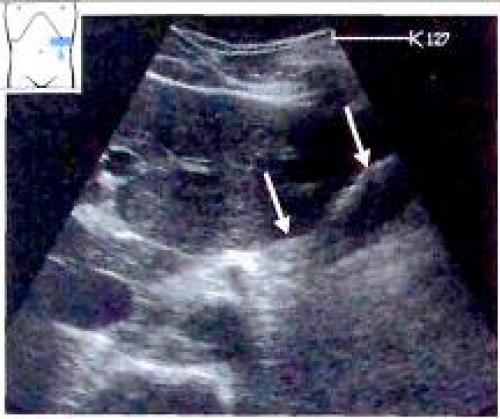

К структурам, которые, как правило, хорошо видны при ультразвуковом исследовании, относятся кардия и гастроэзофагеальный переход, антральный отдел желудка, а также двенадцатиперстная кишка. При этом печень играет роль ультразвукового окна. Качество же визуализации дна и тела желудка спереди или через селезенку (ультразвуковое окно) оставляет желать лучшего. Кардиальный отдел желудка чаще и лучше всего удается визуализировать на продольном сечении, когда желудок определяется между печенью и аортой.

Рис. 3. Визуализация гастроэзофагеального перехода на продольном сечении

Рис. 4. Визуализация гастроэзофагеального перехода на поперечном сечении: Виден срез тела желудка, заполненного неоднородным содержимым (v

В качестве примера патологии кардиального отдела желудка, выявляемой сонографически можно привести его карциному (Рис 5).

Рис 5. а, b Гастроэзофагеальное сочленение (включает кардиальный отдел и входной отдел желудка), а На снимке в косой продольной плоскости, проходящей через верхнюю часть брюшной полости, определяется нормальная гипоэхогенная стенка (мышечный слой) кардиального отдела и свода желудка, b Карцинома кардиального отдела желудка: неправильной формы, гипоэхогенное опухолевое образование, продолжающееся от кардиального отдела пищевода (ES) до свода желудка (F). АО - аорта.